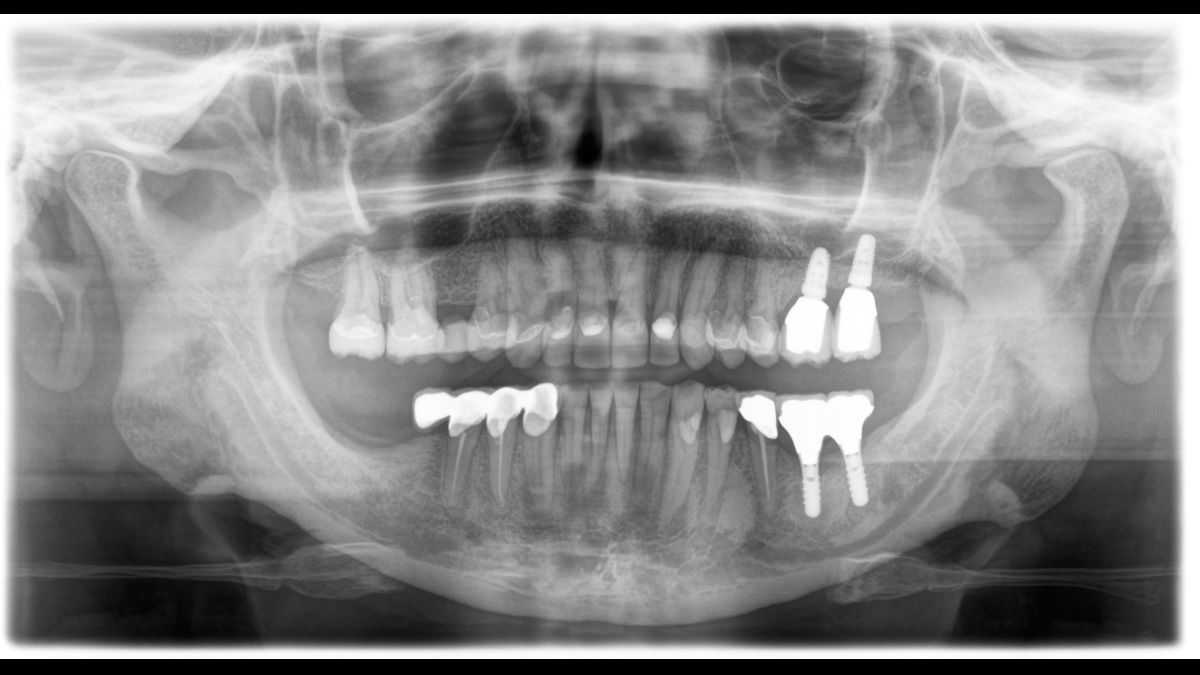

El equipo de radiología 2D/3D de alta calidad con una amplia gama de servicios para cada clínica. Ya sea como un dispositivo puramente 2D o como un módulo 3D, el Orthophos S es un socio confiable y está optimizado para las tareas diarias. Su sensor CsI Plus con función de autofoco garantiza imágenes claras, incluso en casos anatómicamente difíciles. El posicionamiento automático del paciente junto con el bloque de mordida oclusal patentado permite un posicionamiento del paciente fácil y que ahorra tiempo. Para su uso en ortodoncia, la Orthophos S también está disponible con un brazo cefalométrico opcional. Y como para Dentsply Sirona es importante estar preparado para el futuro, el brazo cefalométrico se puede reacondicionar en cualquier momento.

Para la mayoría de las clínicas, se utiliza un equipo de radiología con dos objetivos principales en mente: capturar la mejor imagen posible para respaldar un diagnóstico preciso y exacto, y garantizar que el paciente se sienta cómodo durante el proceso. El Orthophos S ofrece soluciones únicas y patentadas para apoyar ambos objetivos con:

El enfoque correcto es crucial para excelentes radiografías panorámicas. Con la función de autofoco, usted recibirá automáticamente una imagen con la mejor nitidez posible en foco. Los dispositivos de radiología de Dentsply Sirona toman varios miles de imágenes individuales en un ciclo e identifican automáticamente las áreas donde la mandíbula está posicionada de manera óptima. Luego, sin ningún paso manual adicional, estas imágenes se muestran en una nítida imagen final.